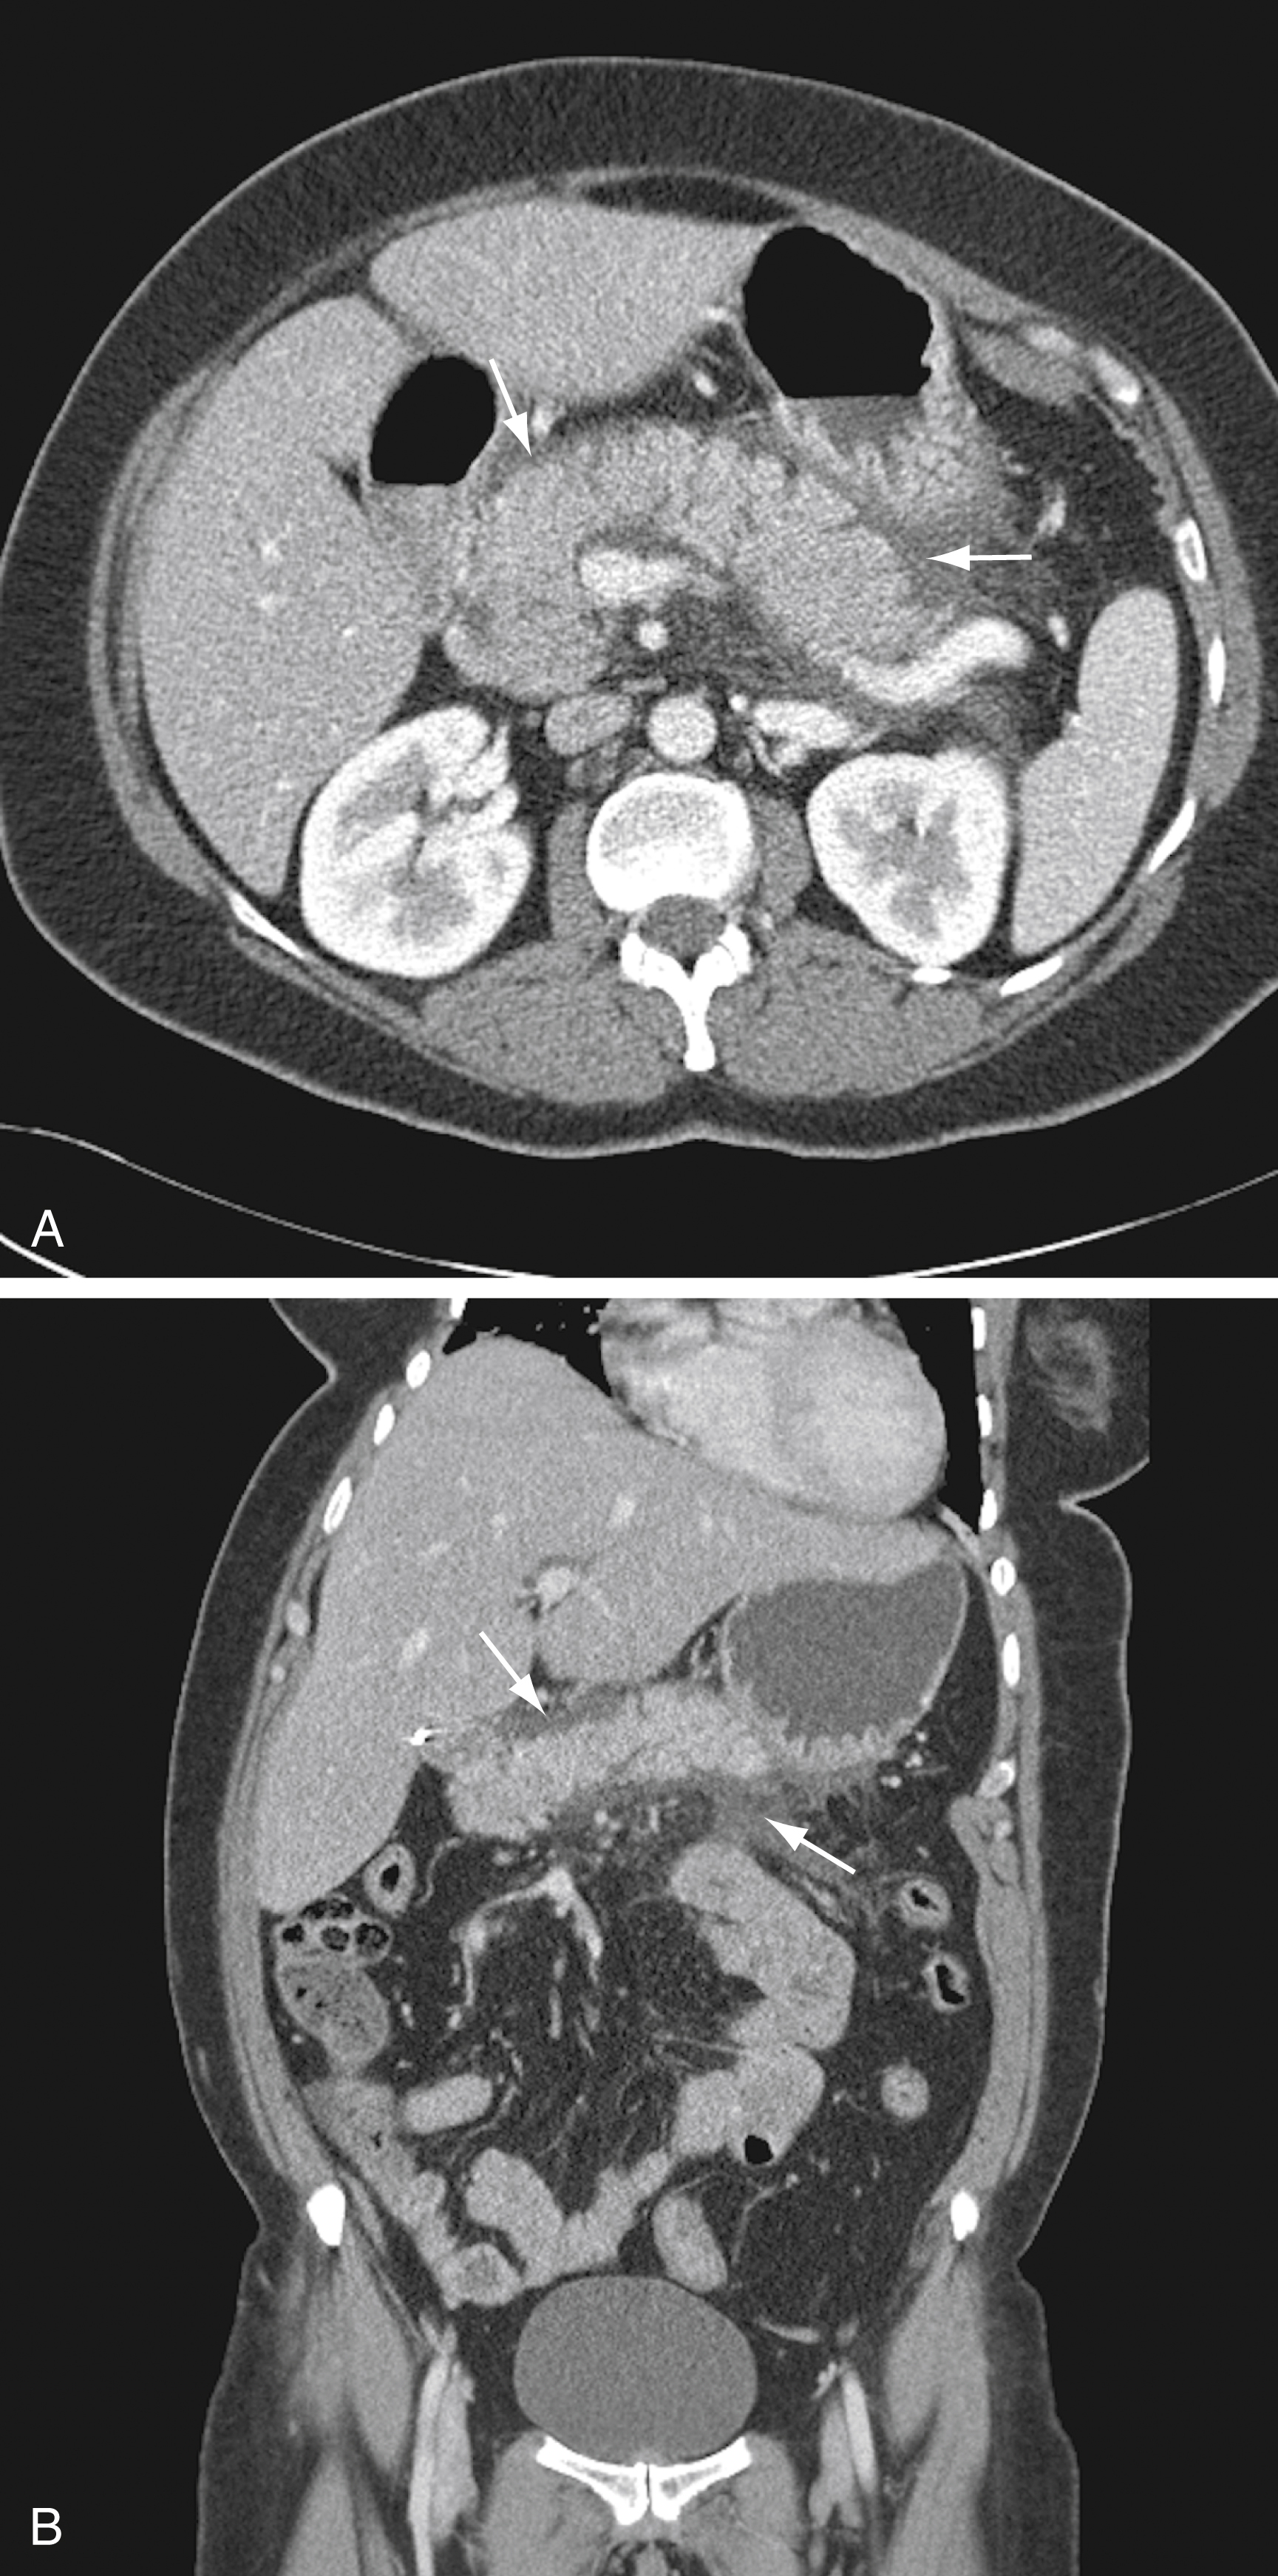

If CT is performed, it should be done with intravenous (IV) contrast. The CT scan is normal in 15% to 30% of patients with mild cases of pancreatitis. Contrast-enhanced CT has a greater than 90% sensitivity and specificity in the diagnosis of acute pancreatitis. Abnormal findings include pancreatic parenchymal enlargement with lack of enhancement, loss of its typical texture and borders, and surrounding retroperitoneal fat stranding ( Fig. 77.2 ). Pancreatic necrosis is suggested by areas demonstrating no enhancement ( Fig. 77.3 ). In cases for which contrast is contraindicated, CT without contrast may still be useful; alternatively, MRI can be performed.

Computed Tomography Scan Showing Acute Interstitial Pancreatitis With Mild Peripancreatic Fluid and Fat Stranding (Arrows) .

(A) Axial view. (B) Coronal view.

Courtesy Dr. David T. Schwartz.